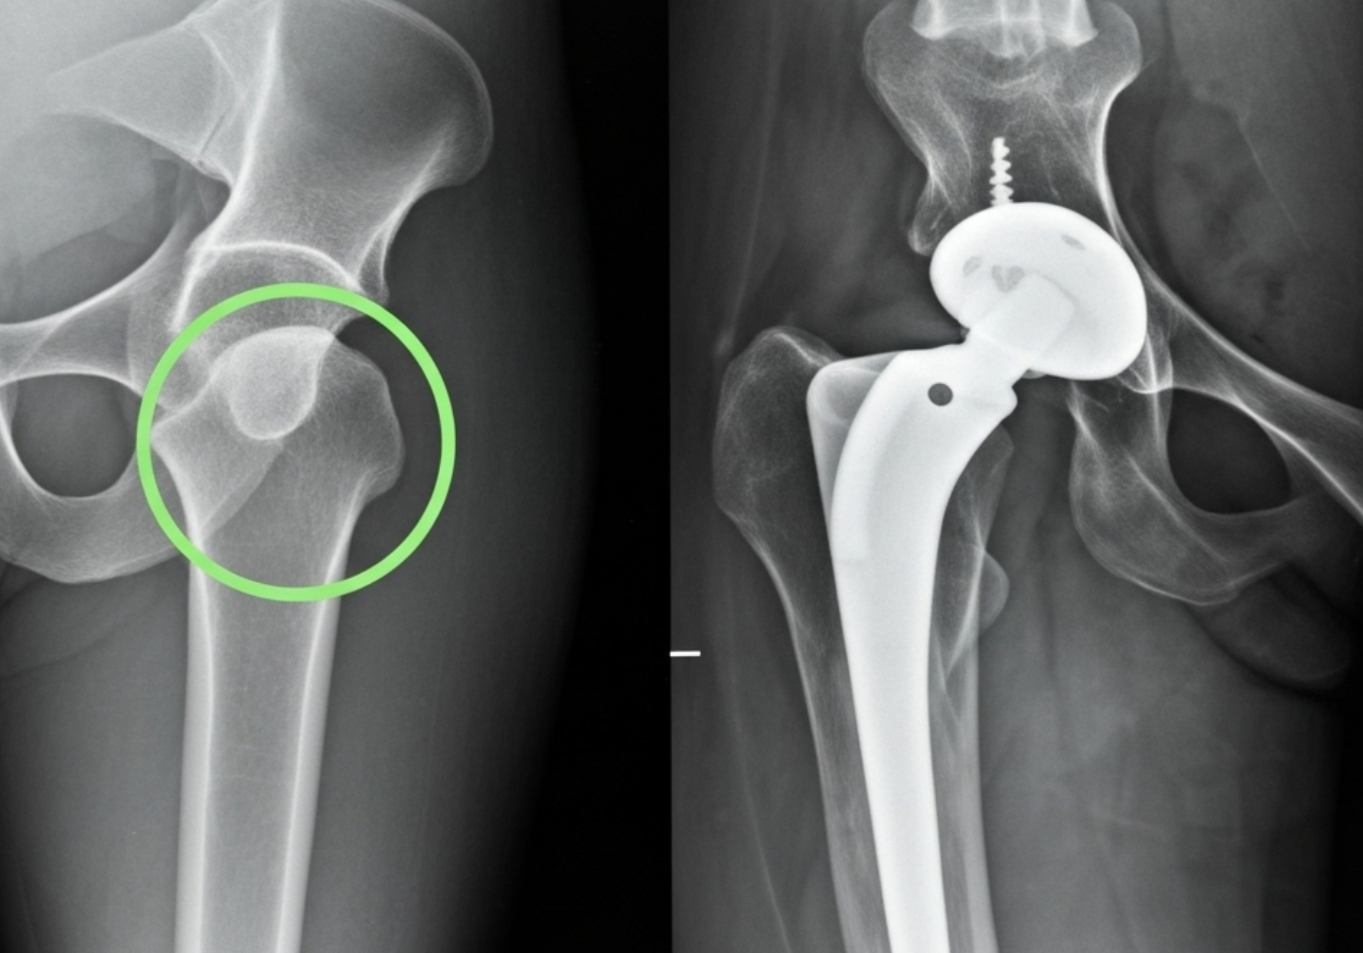

1. 인공관절 전치환술 (Total Hip Arthroplasty, THA)

손상된 고관절 전체(비구와 대퇴골두)를 인공 관절물로 교체하는 수술입니다. 주로 퇴행성 고관절염이나 대퇴골두 무혈성 괴사, 그리고 심한 고관절 골절 등 광범위한 손상이 있을 때 시행돼요. 인공관절은 금속, 세라믹, 플라스틱 등으로 만들어지며, 최근에는 기술 발전으로 수명이 20년 이상으로 길어졌습니다.

2. 부분 인공관절 치환술 (Hemiarthroplasty)

대퇴골두만 인공 관절로 교체하고 비구는 그대로 두는 수술입니다. 주로 고령의 고관절 골절 환자 중에서 비구 관절면의 손상이 적고 활동량이 비교적 적은 경우에 선택됩니다. 전치환술에 비해 수술 시간이 짧고 회복이 빠를 수 있지만, 장기적으로 비구에 부담을 줄 수 있습니다.

3. 골 접합술 (Internal Fixation for fractures)

골절된 뼈 조각을 원래 위치로 맞춘 후 금속 나사나 판을 이용해 고정하는 수술입니다. 주로 젊은 환자의 고관절 골절이나 골두의 괴사 없이 골절만 발생한 경우에 시행하여 자신의 관절을 보존하는 것을 목표로 합니다. 뼈가 잘 붙는 것이 중요하며, 유합 기간 동안 체중 부하를 제한해야 합니다.